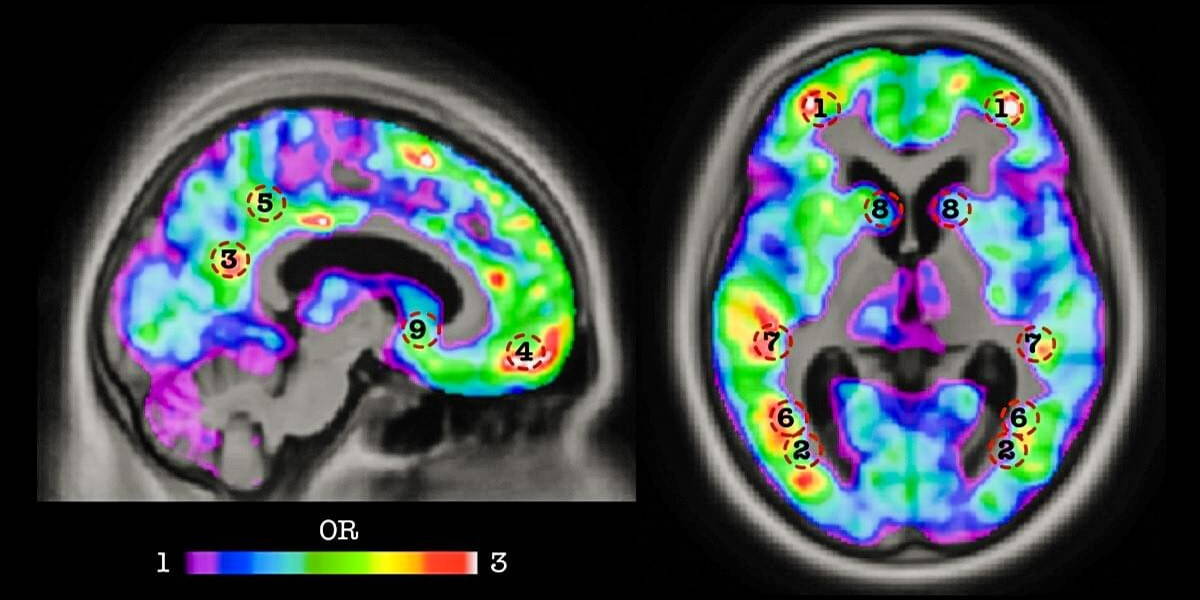

Scientists from McGills Douglas Mental Health University Institute’s Translational Neuroimaging Laboratory, used AI- and big data techniques to develop an algorithm capable of recognizing the signatures of dementia two years before its onset, using a single amyloid PET scan of the brain of patients at risk of developing Alzheimer’s disease. Their findings appear in a new study published in the journal Neurobiology of Aging.

Scientists have long known that a protein known as amyloid accumulates in the brain of patients with mild cognitive impairment (MCI), a condition that often leads to dementia. Though the accumulation of amyloid begins decades before the symptoms of dementia occur, this protein couldn’t be used reliably as a predictive biomarker because not all MCI patients develop Alzheimer’s disease. To conduct their study, the McGill researchers drew on data available through the Alzheimer’s Disease Neuroimaging Initiative (ADNI), a global research effort in which participating patients agree to complete a variety of imaging and clinical assessments.

Hundreds of amyloid PET scans of MCI patients from the ADNI database were used to train the team’s algorithm to identify which patients would develop dementia, with an accuracy of 84 percent, before symptom onset. Research is ongoing to find other biomarkers for dementia that could be incorporated into the algorithm in order to improve the software’s prediction capabilities.